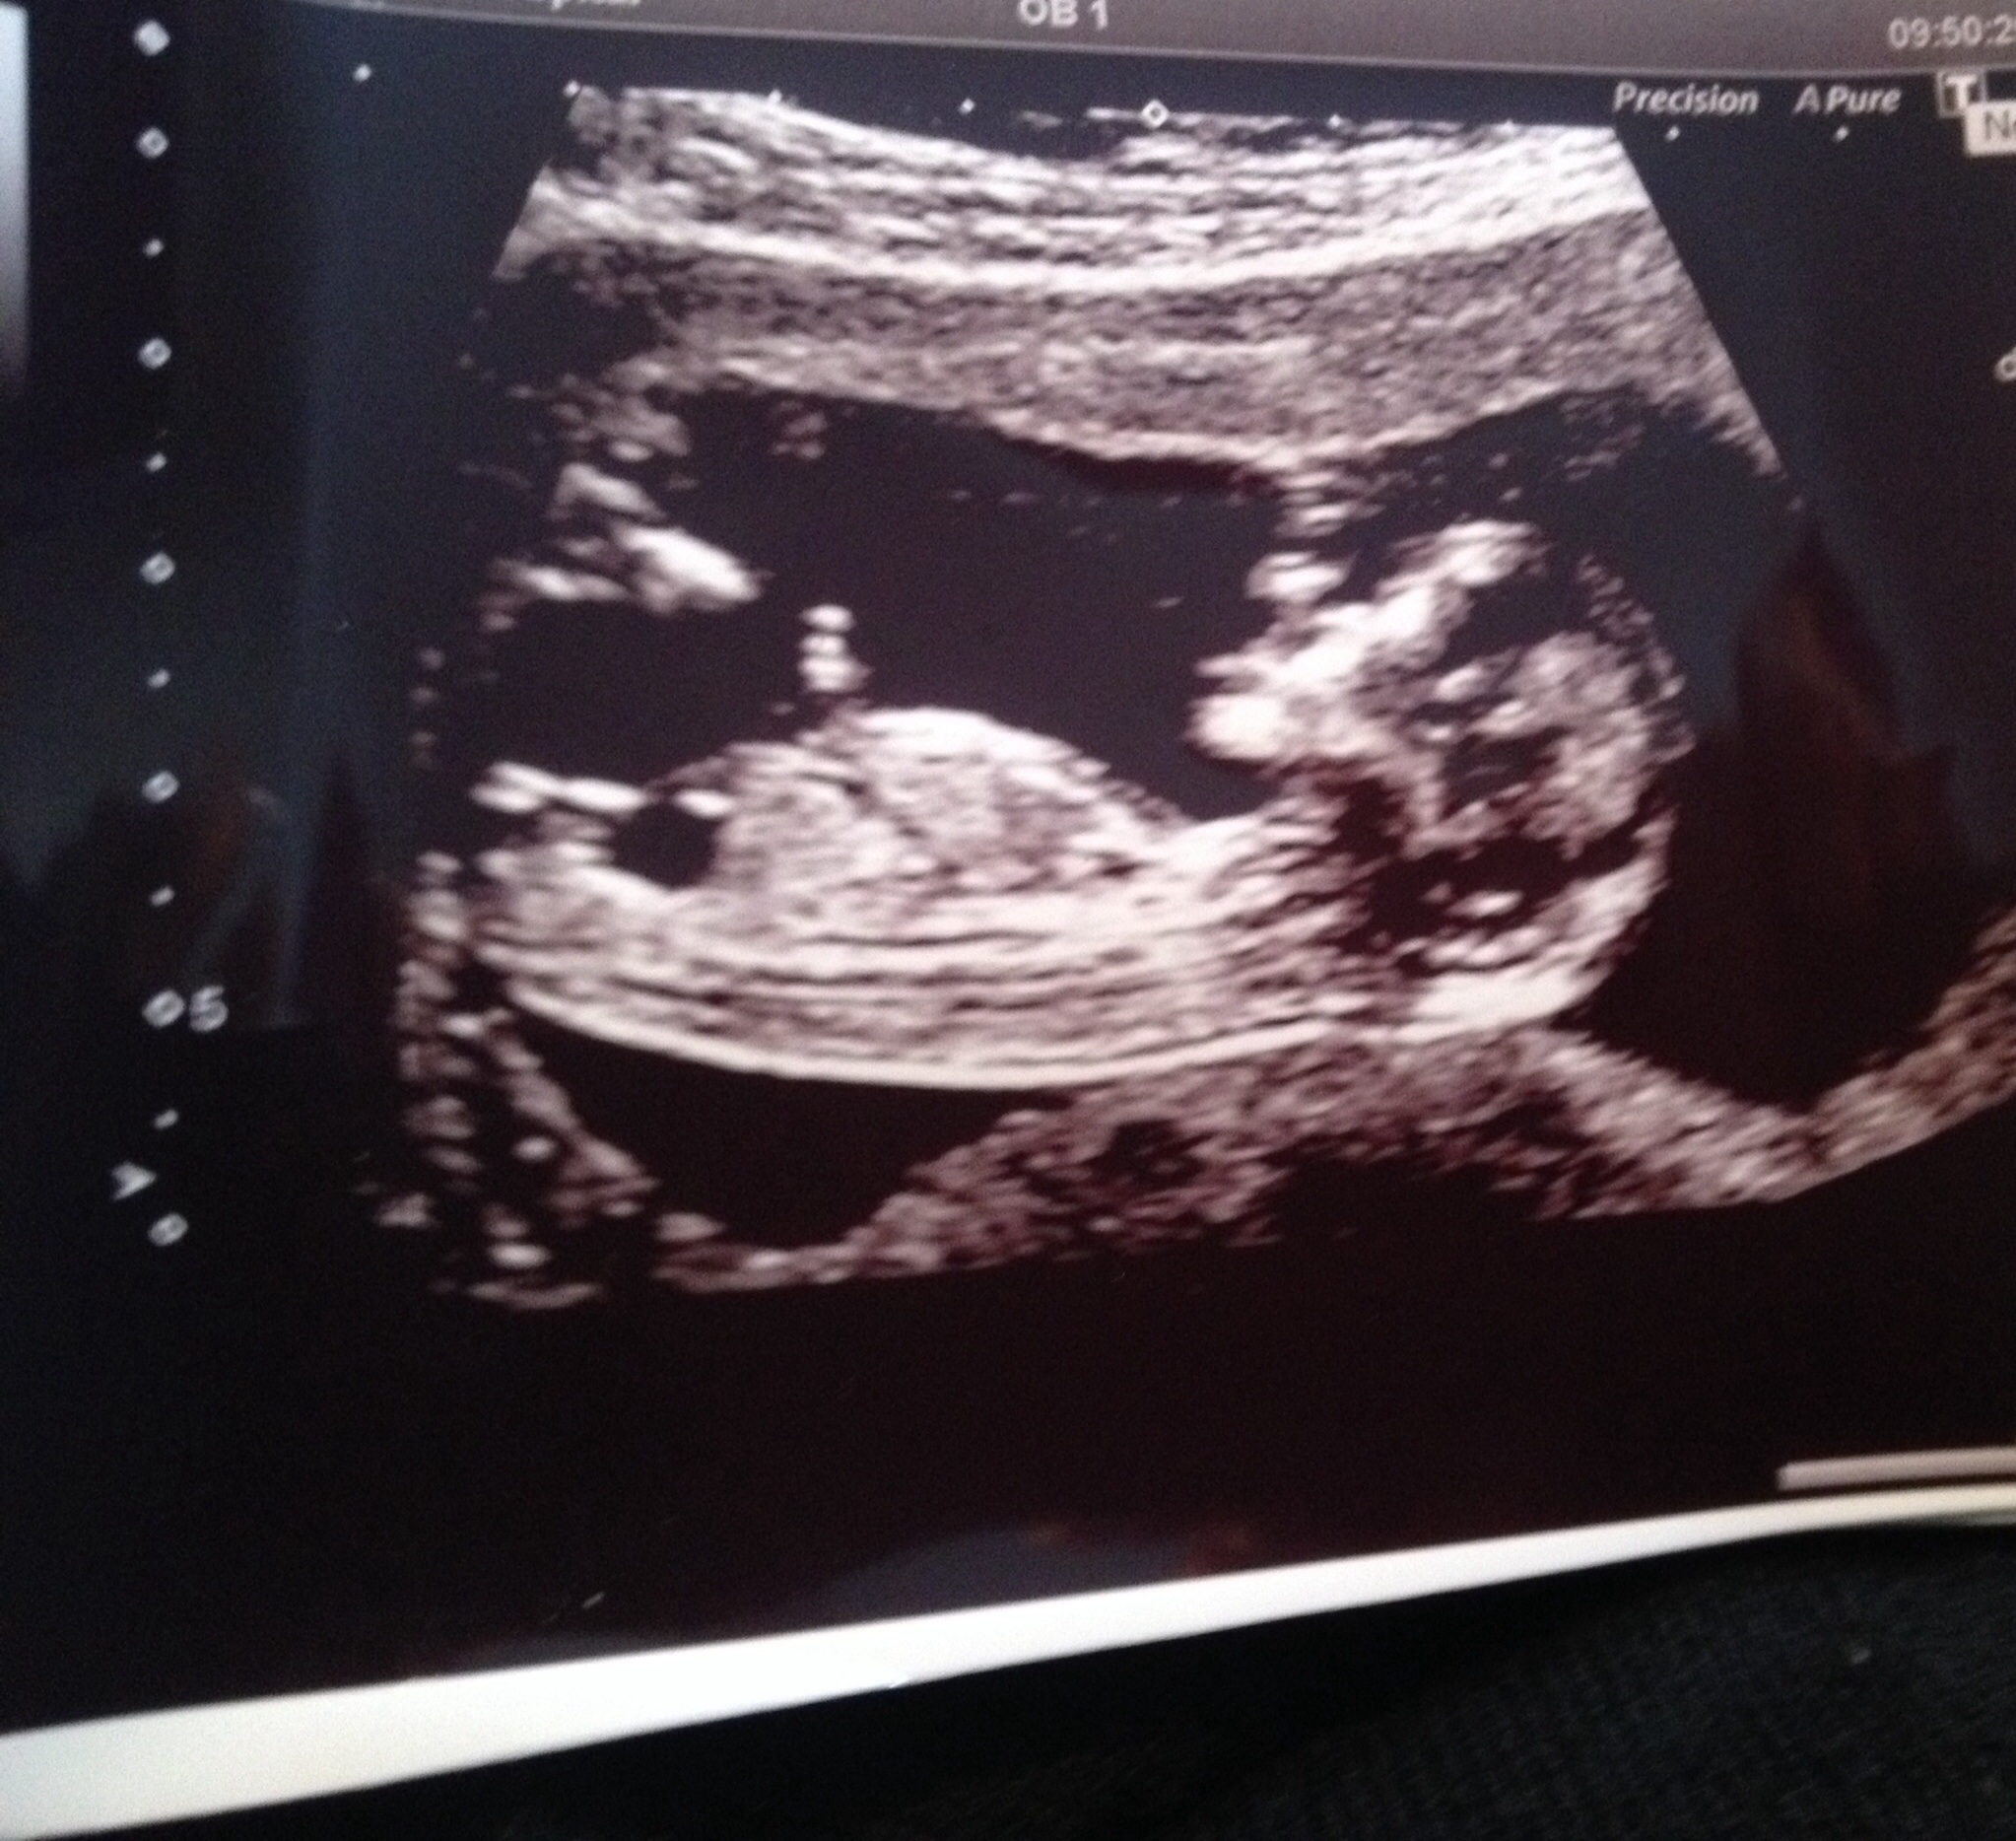

Leaning pink since it's 13 weeks xx